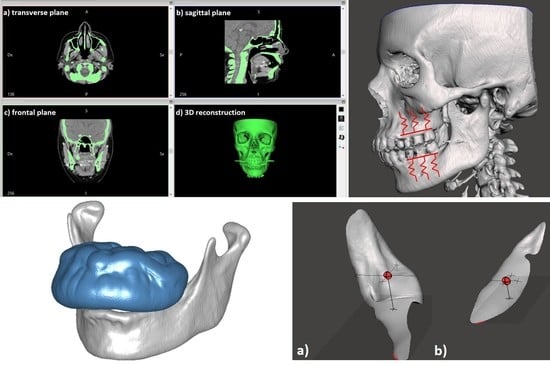

2.2. Case Study of a Maxillary Exostosis: Congruence and Contact Evaluation